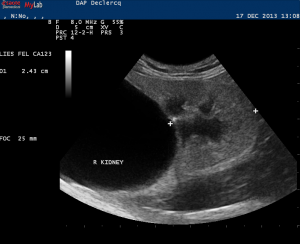

Diagnostic?

Petite tumeur rénale droite trouvée de manière fortuite sur un scanner